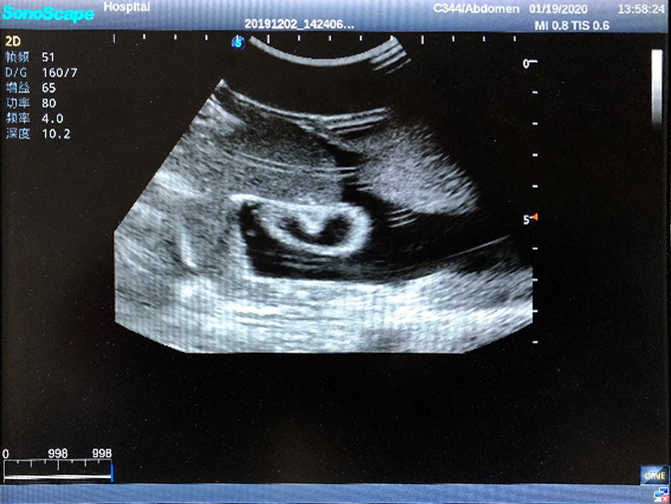

2)  High quality ultrasound image with clear structures like gallbladder, liver, intestines, arteries and veins etc.

5)  Normal & pathological ultrasound live and intestine models inside